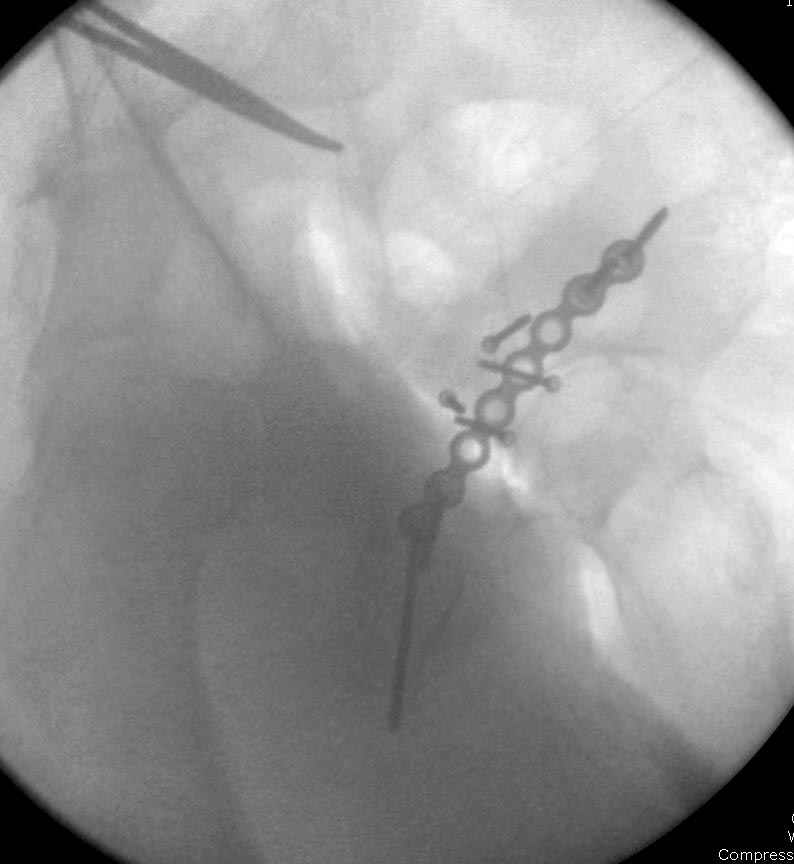

6:20 ответстенный врач принимает решение о репозиции в условиях операционной, предупреждаются родственники и больной, что при неудачной закрытой репозиции, о возможности открытой репозиции и фиксации задней стенки вертлужной впадины.

7:30 начало операции, больной на спине, попытка репозиции после анестезии N3, укладка больного на боку, доступ Kocher- Langenbeck, состояние седалищнего нерва около 2.5см кровоподтек, через joistick головка бедра приподнята, освобовождение сустава, фрагмент заднего края более 3х4 см репонирован на свое место. После промывания